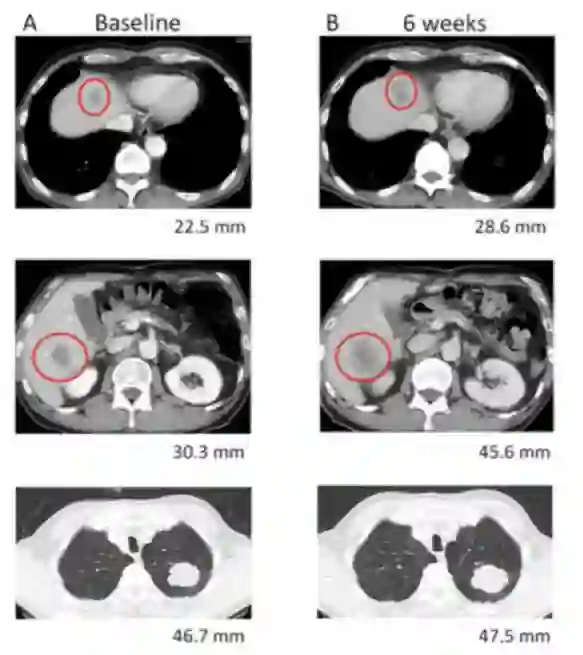

*纳武利尤单抗治疗6周后评价:肝脏病灶增大,血清CEA降低。

图1. 患者初诊(A)、纳武利尤单抗治疗6周(B)肝转移灶和肺原发灶的CT影像

对于免疫治疗后病灶增大,但是血清CEA水平下降,患者症状及体征好转且耐受性良好的情况下需要综合考虑 ,排除假性进展可能,该类人群也可能是免疫治疗获益人群。该患者选择了继续使用纳武利尤单抗免疫治疗,12周后复查CT提示原发灶和转移灶均缩小,血清CEA持续下降,故该患者考虑为假性进展。